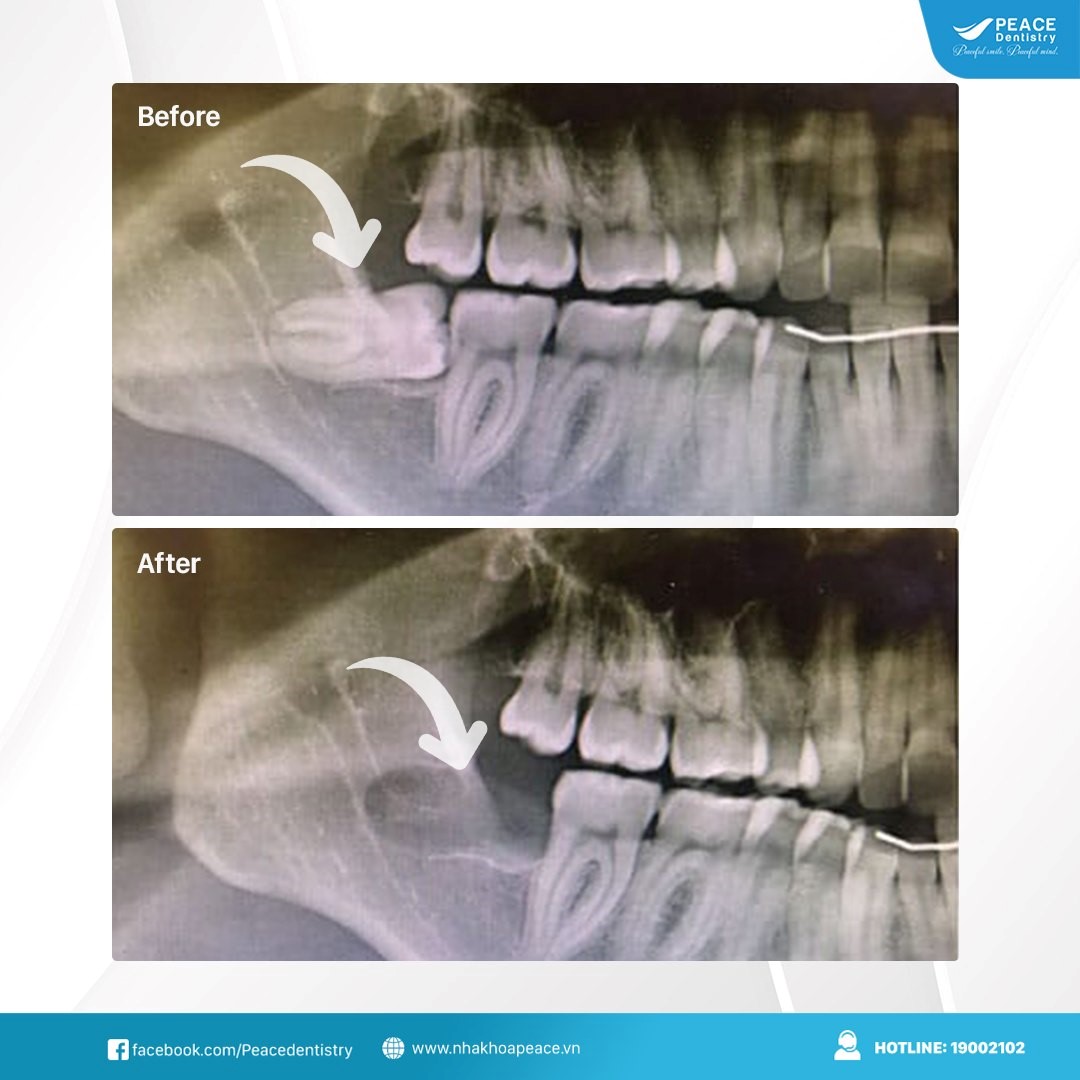

Nếu răng khôn mọc lệch, mọc ngầm bạn nên tiến hành nhổ sớm để tránh các biến chứng nguy hiểm. Sau khi nhổ răng tình trạng lợi trùm có mủ cũng sẽ được khắc phục hoàn toàn

(Kết quả nhổ răng khôn được thực hiện tại Peace Dentistry)(**)